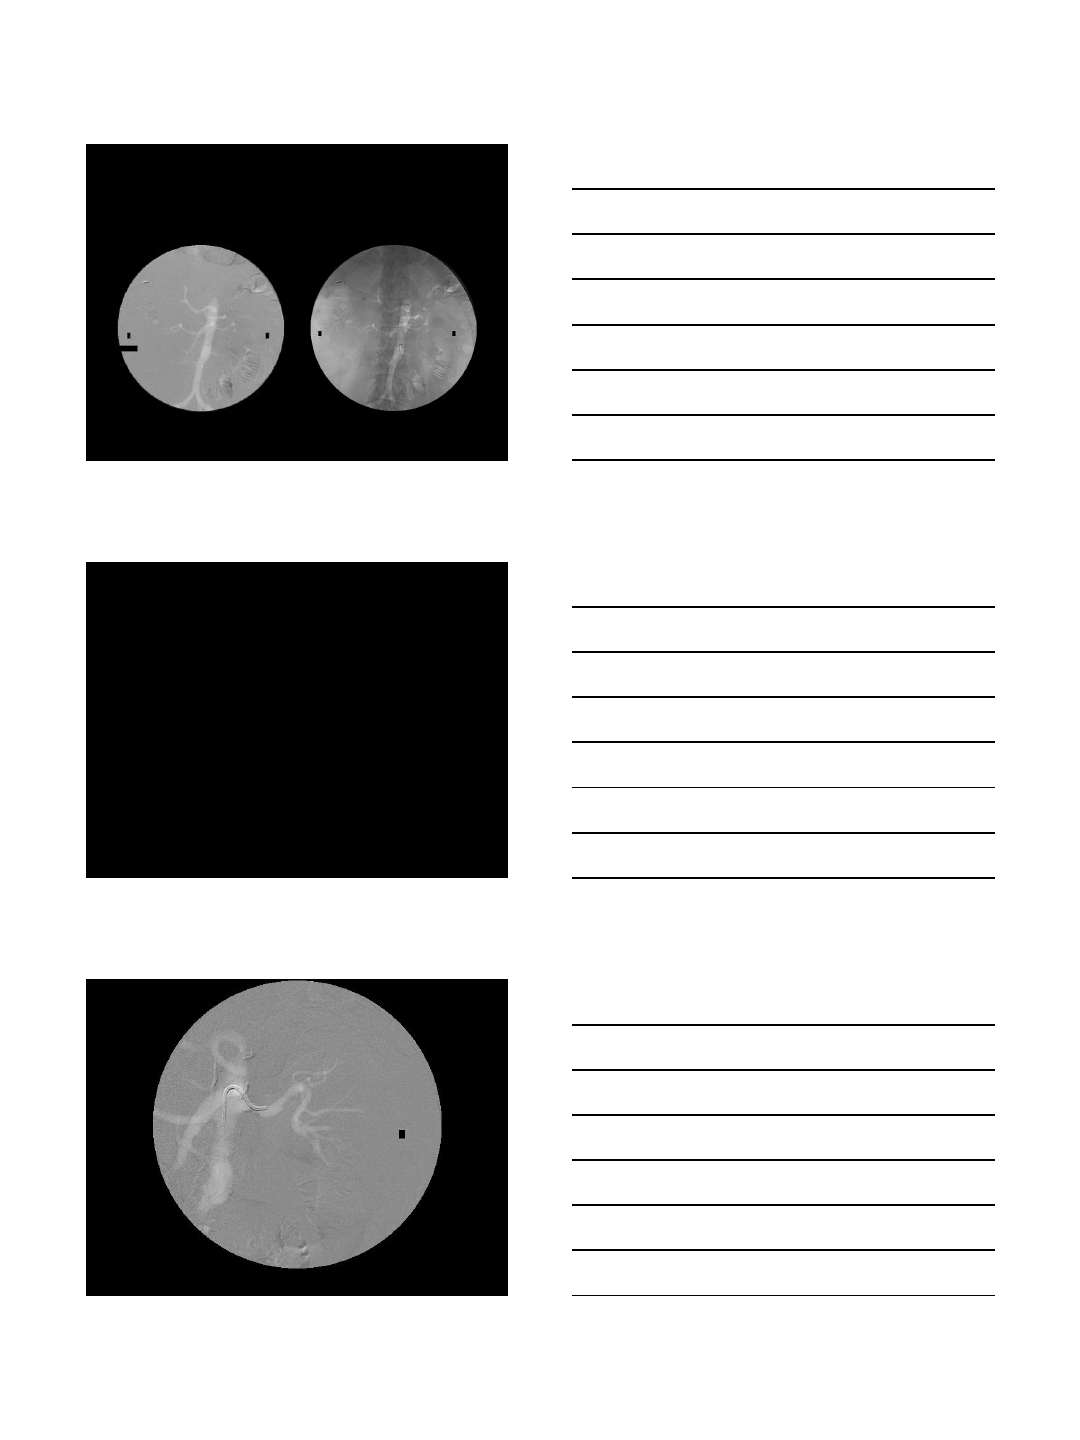

Carbon Dioxide Imaging

Subtracted Image Aorta filled with CO2 -

unsubtracted image

Carbon Dioxide Imaging with

Interventions